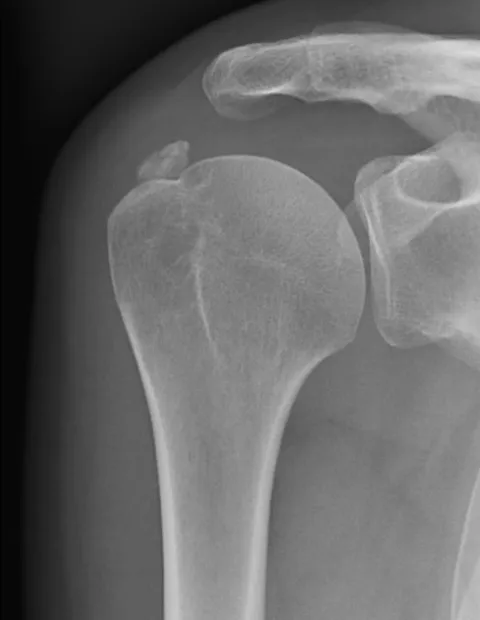

Les calcifications sont des dépôts calciques situés au sein du tendon. Elles sont fréquentes, mais le plus souvent asymptomatiques. Elles peuvent être situées dans tous les tendons de la coiffe, plus rarement au niveau du tendon du long biceps.

Elles sont parfois découvertes de façon fortuite sur des radiographies sans que le patient ne présente de symptômes au niveau de son épaule.

Le plus souvent elles sont découvertes au cours (ou au décours) d'un épisode douloureux associé à une impotence fonctionnelle majeure.

C'est ce que l'on appelle "l'épaule aigüe hyperalgique".Ces phénomènes douloureux sont causés par la rupture de la calcification qui est une petite poche contenant des cristaux de calcium, qui, une fois libérés déclenchent un phénomène inflammatoire très douloureux.

Dans un premier temps des radiographies et une échographie permettent d'avoir une orientation diagnostique en corrélation avec l'examen clinique du chirurgien. Ces examens permettent de vérifier l’absence d’arthrose, et de confirmer ou non la présence d’une lésion tendineuse ou d’une calcification. Il s’agit du bilan de débrouillage qui sera complété le plus souvent par un arthro-scanner ou une IRM.